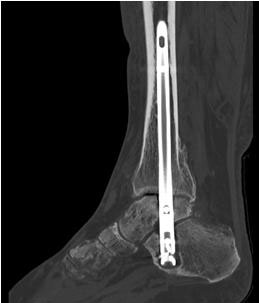

Durch die Fusion des oberen und unteren Sprunggelenkes soll eine Schmerzfreiheit bei gleichzeitiger Stabilität und Belastbarkeit in den genannten Gelenkabschnitten erreicht werden. Die Mobilität des Patienten bleibt damit gewährleistet. Durch Resektion der Gelenkflächen im OSG und im USG kann die Achse im Sprunggelenk korrigiert werden 67. Die Retention erfolgt durch einen von plantar aus eingebrachten Verriegelungsnagel. Orthopädietechnische Schuhzurichtungen oder sogar die Anpassung von orthopädischen Massschuhen sind nach einer Versteifungsoperation im OSG und USG häufig sinnvoll.

Implantation des Nagels und BV-Kontrolle (Video 5). Schließlich erfolgt die Verriegelung des Nagels über entsprechende Zielvorrichtungen. Bei einigen Nageltypen gibt es nageleigene Kompressionsmechanismen, die eine zusätzliche Drucksteigerung im Bereich der Arthrodeseflächen des ehemaligen oberen und unteren Sprunggelenkes erlauben (Video 6). Die abschließende BV-Kontrolle in beiden Ebenen sollte eine regelrechte Stellung der Arthrodese mit 90° - Stellung im Rückfuß, in der anderen Ebene mit einem Rückfußvalgus von ungefähr 5° zeigen.